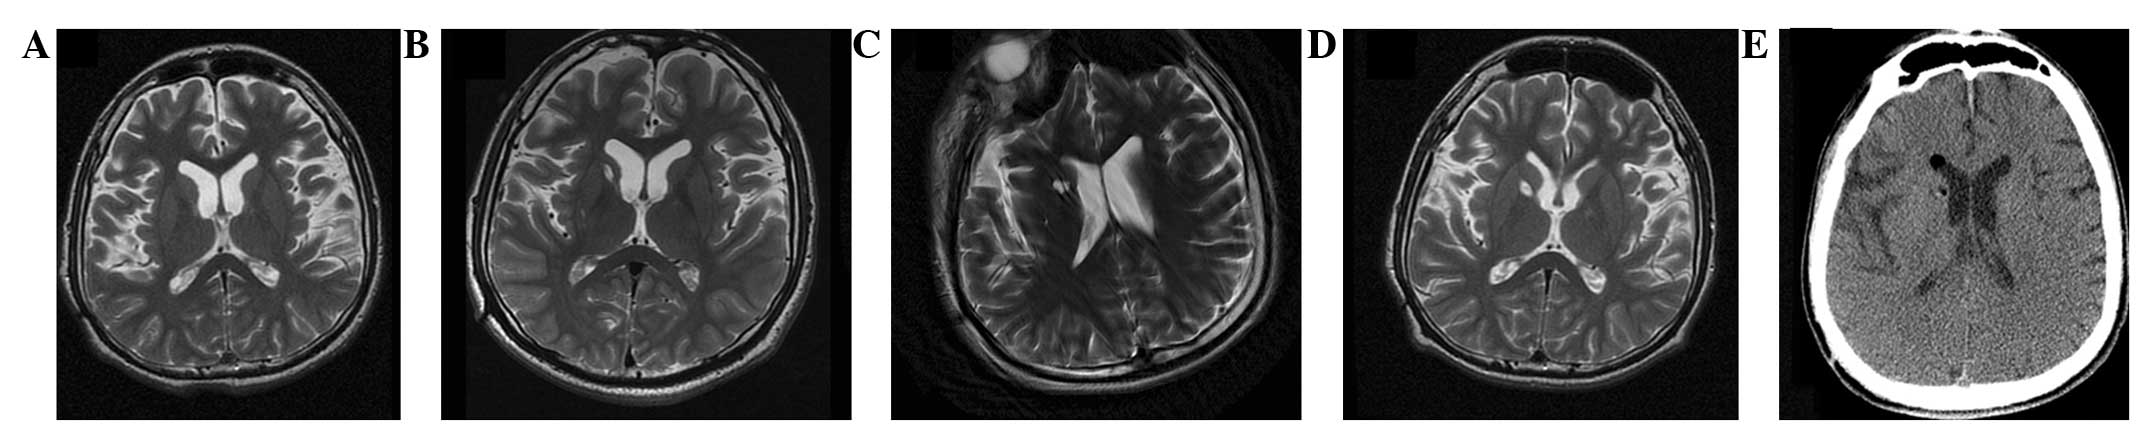

本研究選擇的患者為18歲男性,患有PTD,預產期剖宮產出生,無任何遺傳病家族史,無腦炎、黃疸、腦腫瘤病史或外傷。他在5歲時首次出現左下肢不自主痙攣和扭轉,沒有任何誘發因素。臨床特征從5歲至9歲逐漸擴展到全身。18歲時,患者無法書寫、抓握、站立或行走。他吞咽固體食物有些困難,但沒有癲癇癥狀。患者智力正常。頭部計算機斷層掃描(CT;圖1a)和磁共振成像(MRI;圖2a)提示大腦輕度萎縮。PTD是根據上述數據診斷的。

(A) 術前 MRI 顯示腦萎縮。 (BD)術后1年、3年、4年MRI與術前MRI相比無明顯變化。 (E) 術后3天,計算機斷層掃描顯示沒有出血或水腫。

遺傳分析發現患者DYT1 ( TOR1A )第五外顯子存在突變 (907-909 delGAG) 。他對神經外科手術表現出良好的耐受性,并于4點出院。沒有與細胞植入或外科手術相關的嚴重不良事件。POD時的CT掃描顯示沒有出血或水腫(圖2e)。術后1個月,患者的PTD癥狀開始改善。BFMDMS逐漸增加,從術前的21分別增加到術后1、2、3和4年的18、17、15和13,術后4年改善38.1%(表1)。

CT(圖1b-e)和MRI(圖2b-d)掃描顯示4年隨訪期間沒有顯著變化。 手術前1天(圖1f)和手術后1、2、3和4年(圖1g-j) 獲得18F-FDGPET掃描。術后雙側植入部位豆狀核和丘腦18F-FDG攝取值較術前增加。這一結果表明,自移植以來,葡萄糖代謝逐年略有增加。